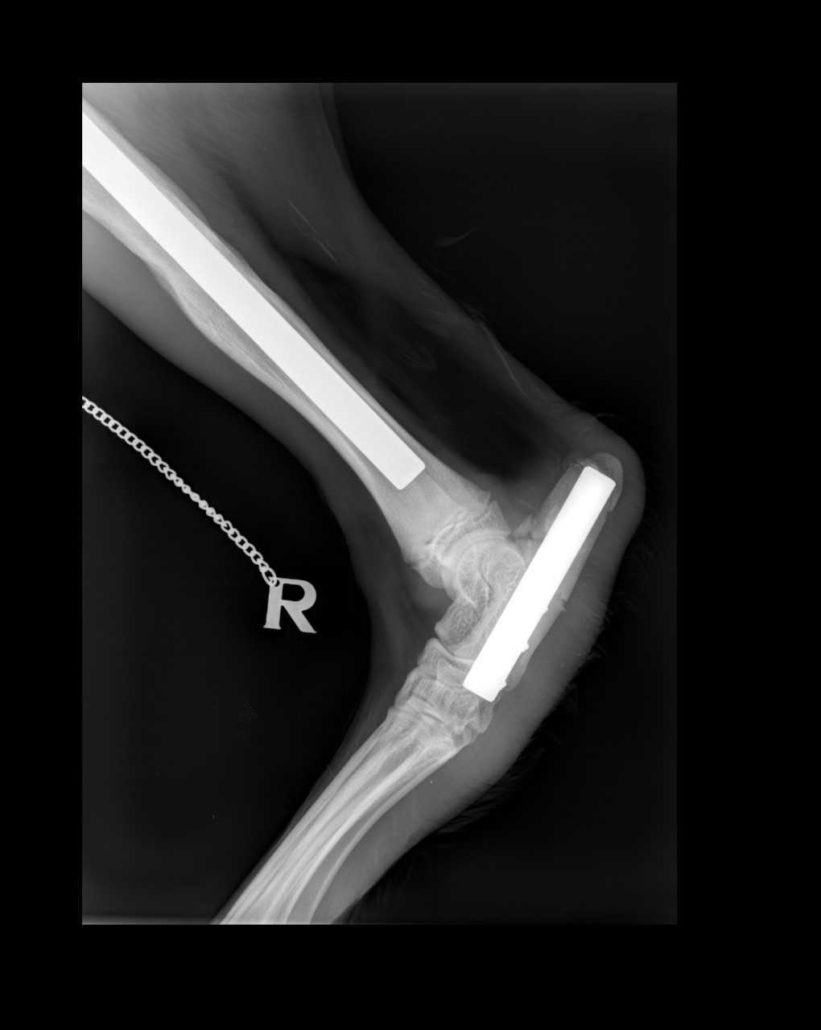

Speed heeft een zeer ernstige breuk opgelopen in zijn achterpoot in de zoo waar hij geboren is. Bij het klimmen op een hek is zijn achterpoot vast blijven zitten met een complexe breuk tot gevolg in de hiel en het onderbeen.

Met orthopedische platen is de breuk gefixeerd. Eind maart van dit jaar zijn hierbij problemen ontstaan omdat de orthopedische plaat doorheen de huid kwam. Hierbij ontstaat een groot risico voor infectie dus de plaat moest verwijderd worden. Hiervoor schakelden we de Ugent in, waar specialisten van anesthesie (verdoving) en orthopedie uren gewerkt hebben aan het verwijderen van de plaat. Er is hierover al een artikel verschenen: https://pakawipark.eu/dierenniews/run-speed-run/

Helaas is er bij het verwijderen van de plaat, wat erg complex was, waarschijnlijk een microfractuur ontstaan waardoor enkele weken later de poot terug gebroken is. Vervolgens is er dan opnieuw een orthopedische plaat gestoken door dierenartspraktijk Orion. Helaas brak enkele dagen later zelfs de stalen plaat. Opnieuw werd er een plaat gestoken, deze keer een dikker en zwaarder exemplaar.